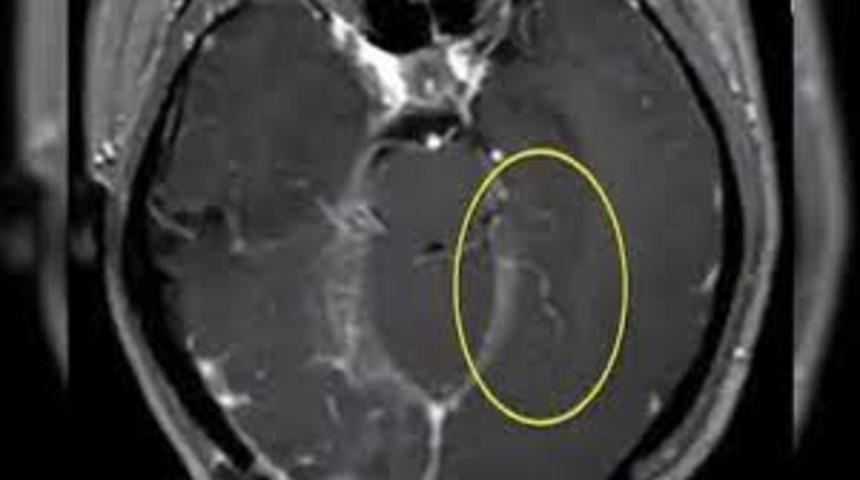

Avustralya’da yaşayan ismi açıklanmayan 64 yaşındaki bir kadın ilk olarak 2021 yılında üç hafta süren karın ağrısı ve ishal ardından gelen kuru öksürük ve gece şikayetleri nedeniyle hastaneye kaldırılmıştı. Septomların unutkanlık ve depresyona dönüşmesi üzerine yeniden hastaneye başvurmak zorunda kalan 64 yaşındaki kadının beyninin MRI taramasında beyninin sağ ön lob lezyonunda hareketli bir solucanın (parazitik bir yuvarlak kurt) yaşadığını ortaya çıkardı.

MRI sonucunun ardından cerrahi müdahale tek seçenek haline geldi ve doktorlar uzunluğu 8 cm (80 mm) ve çapı 1 mm olan yuvarlak kurdu başarıyla çıkardı.